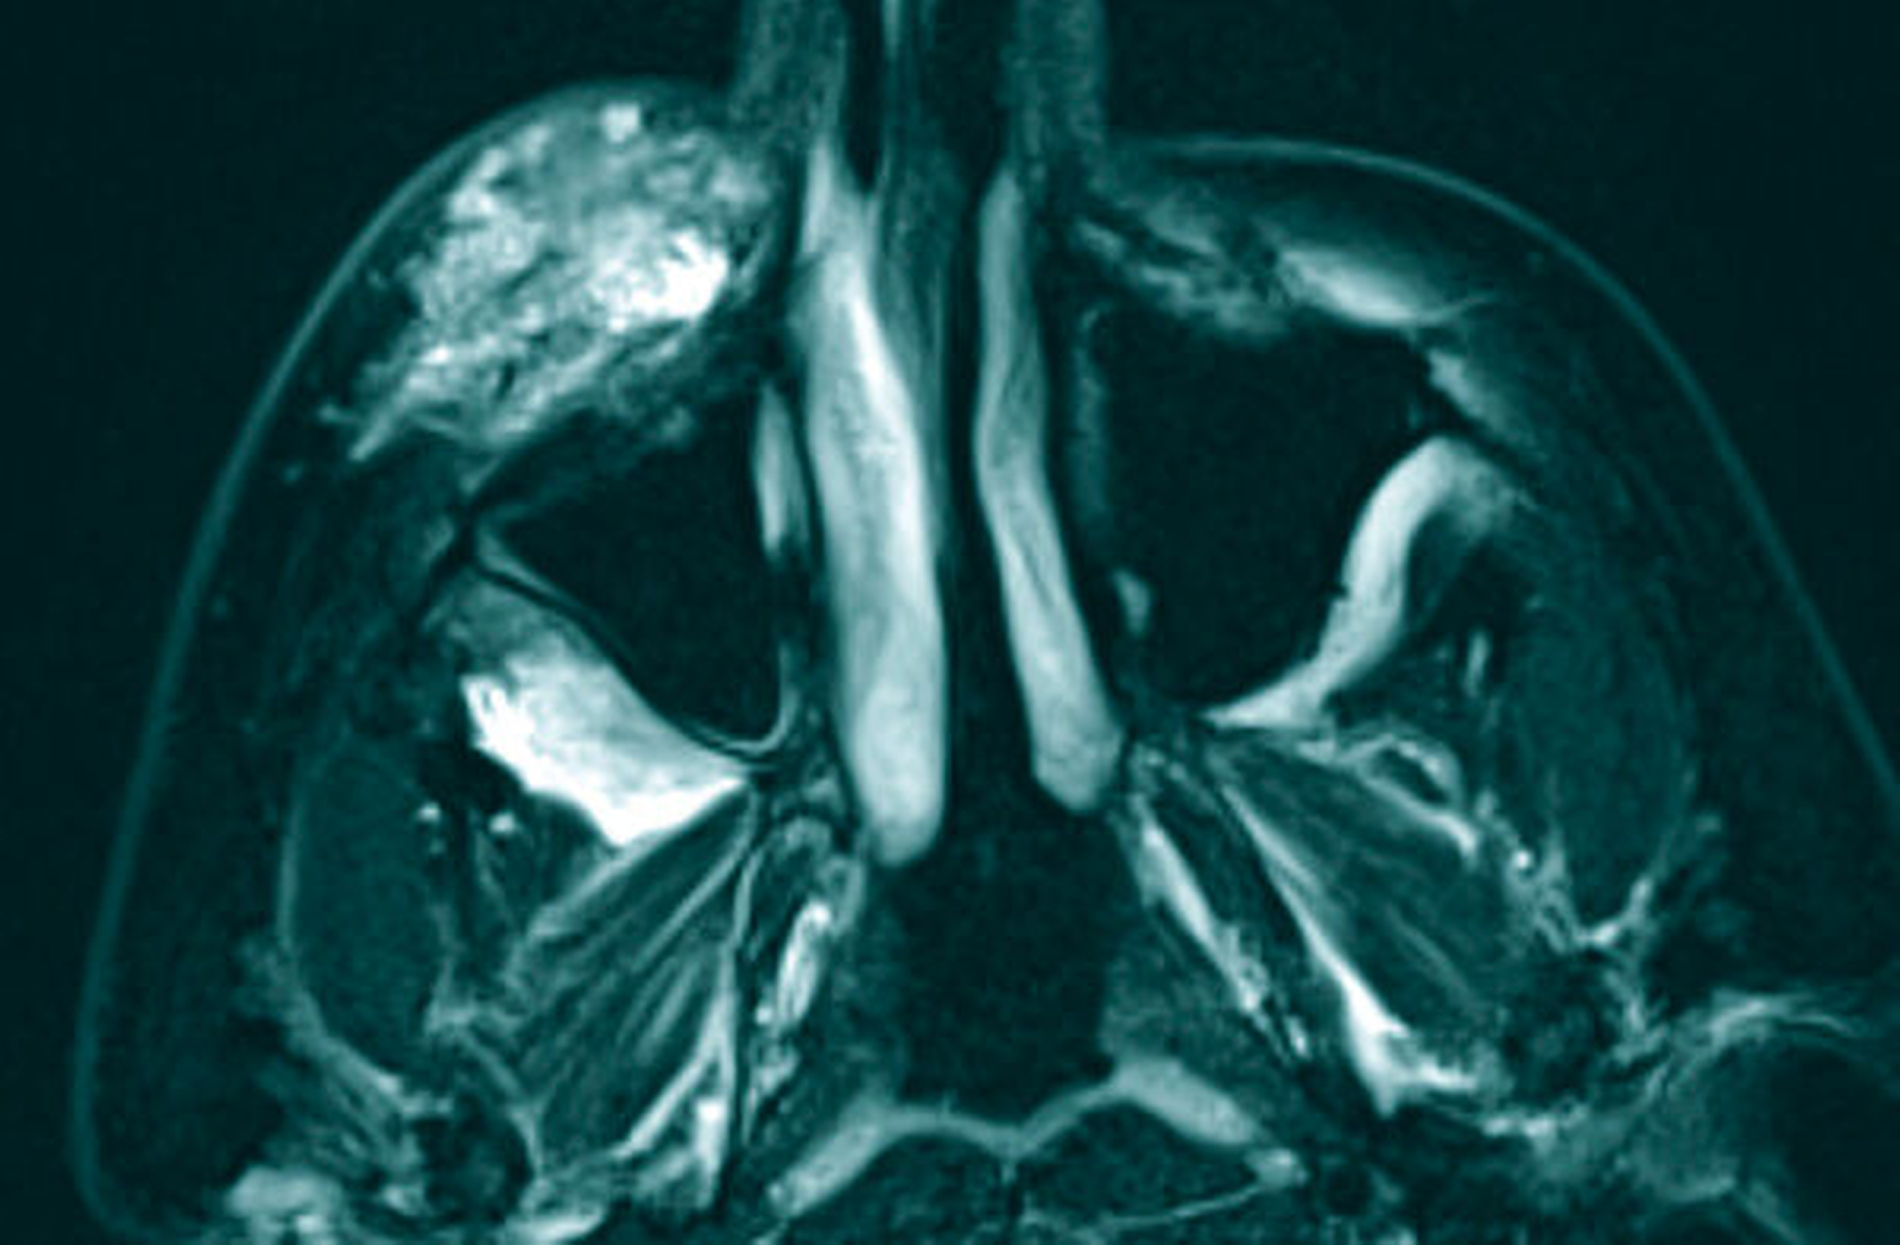

Zur Beurteilung der Befundausdehnung und zur Planung der Therapie wurde präoperativ eine Magnetresonanztomografie (MRT) des Schädels angefertigt (Abbildung 2). Hier zeigte sich die bekannte vaskuläre Malformation der rechten Wange mit Ausläufern nach intraorbital, in die Fossa pterygopalatina und infratemporalis. Im Vergleich zu den Voraufnahmen zeigte sich eine geringe Größenprogredienz des extraorbitalen Befunds (Abbildung 3).

Nach präoperativer Sklerosierung des Wangenhauptbefunds (Abbildung 4) erfolgte am Folgetag die Resektion in Intubationsnarkose. Hierzu wurde nach subziliärer Schnittführung (Abbildung 5) eine scharfe Präparation des Tumors nach kaudal unter Schonung des Ramus buccalis des Nervus facialis durchgeführt (Abbildung 6) und dieser schließlich exzidiert (Abbildung 7). In der histopathologischen Aufarbeitung zeigten sich Muskel-, Fett- und Weichgewebe mit reichlich interponierten, kavernös konfluierenden, blutgefüllten Gefäßformationen unterschiedlicher Größe (Abbildung 8). Der postoperative Verlauf gestaltete sich bis auf eine vorübergehende Einschränkung der Fazialisfunktion im Bereich des Mundastes unauffällig, sodass der Patient zeitnah in die ambulante Weiterbetreuung entlassen werden konnte.